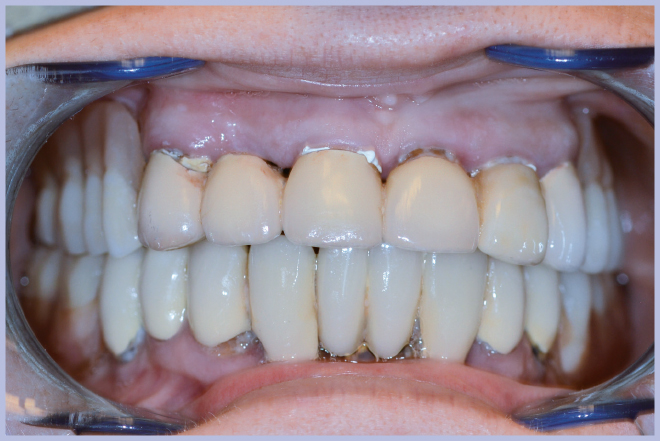

La semplicità della componentistica Leone ha permesso di completare l’intero trattamento in circa 6 ore e mezzo, consegnando alla paziente la protesi ultimata nella stessa giornata della chirurgia (Figg. 11-13).

- Fig. 11 – Consegna della protesi rifinita